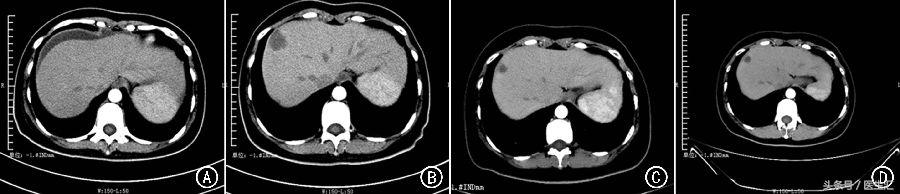

术后妇科超声和腹盆腔CT 显示盆腔积液征象,未见明确占位性病变(图1A)。2014 年11 月19 日至12 月12 日行TC 方案(紫杉醇175 mg/ m2 和卡铂AUC5,静脉滴注) 化疗2 个周期。

2015 年1 月7 日CT 显示肝内新发多发低密度灶,阴道残端区域软组织影,诊断为CCOC术后复发、肝多发转移和腹膜转移,考虑为难治性卵巢癌,CA125 和CA199 分别为58.4 U/ ml和992. 75 U/ ml, 根据实体瘤疗效评价标准( ResponseEvaluation Criteria in Solid Tumors, RECIST ) 1.1 版评价疗效为疾病进展(progressive disease, PD;图1B), 无进展生存时间(progression⁃free survival,PFS)为1.5 个月。

由于患者不同意继续治疗,治疗中止而导致PD,CA125 和CA199 分别为137.6 U/ ml 和3 688.85 U/ ml。于2015 年8 月11 日至2016 年1 月6 日继续行第6~ 11 个周期伊立替康+贝伐珠单抗治疗,治疗后CA125 和CA199 分别为15.4 U/ ml 和124.18 U/ ml,疗效评价为部分缓解(图1C)。

依维莫司治疗2 个月及5 个月后复查盆腔CT,疗效评价为SD(图1D),CA125 和CA199 分别为18 U/ ml 和162 U/ ml。

图1 卵巢透明细胞癌患者的治疗情况 A: 术后腹部CT 显示,腹盆腔积液征象,未见明确占位性表现; B: TC 方案化疗2 个周期后,新发肝脏多发转移及腹膜转移; C: 给予贝伐珠单抗+伊立替康11 个周期后,肝脏、腹膜等多处病灶较前明显缩小; D: 口服依维莫司维持治疗5 个月后,肝脏及腹膜等多处病灶基本稳定